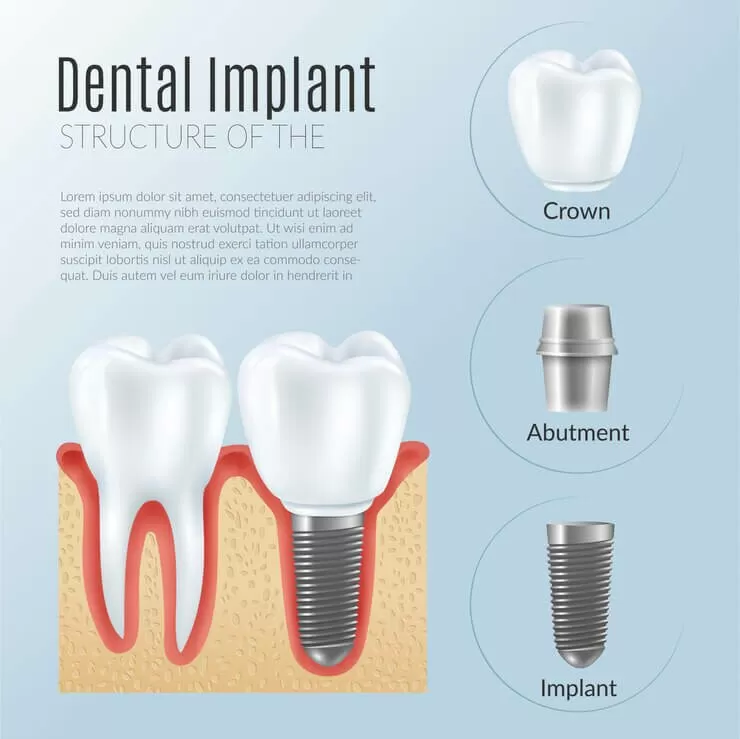

Имплант — винт из титанового сплава, который выступает в качестве искусственного корня. Как правило, он состоит из трех элементов:

- корневая часть, которую вживляют в челюстную кость;

- абатмент — служит опорой для мостовидного ортопедического протеза или коронки;

- коронка, имитирующая натуральный зуб.